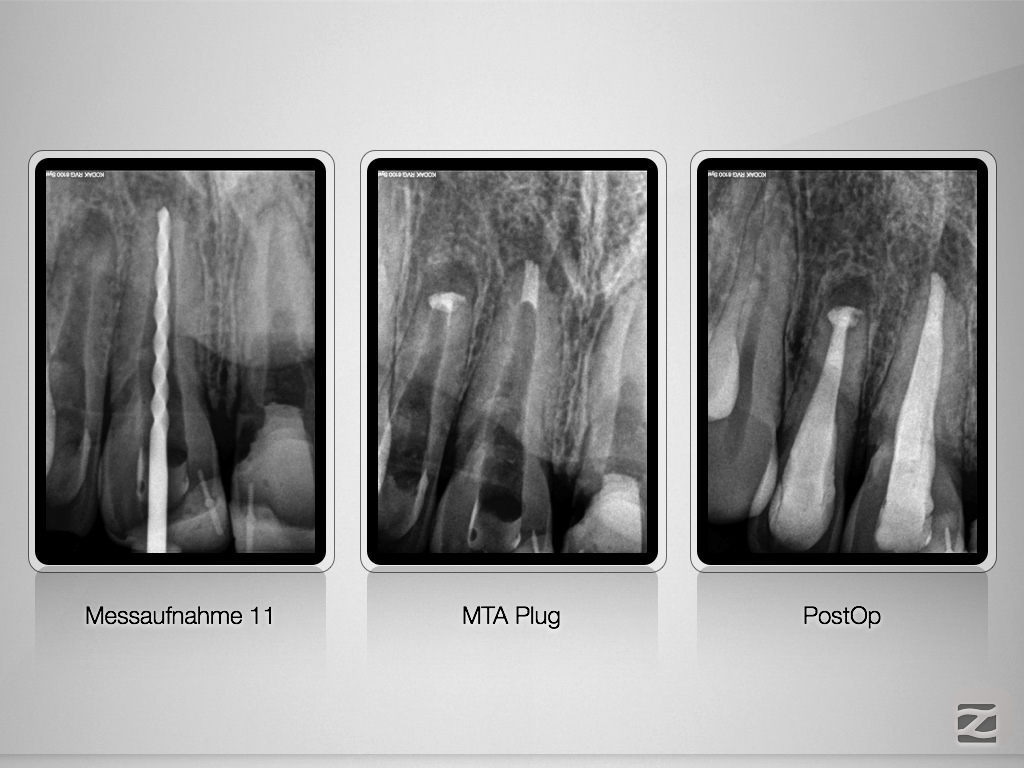

12,11 D.007

Wer hätte es gedacht , …